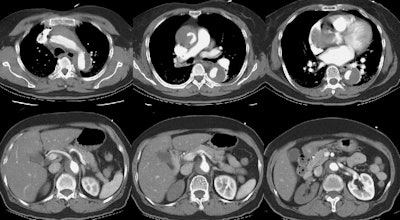

The contrast CT scan revealed an extensive Type A aortic dissection which extended into the aortic root. The true lumen is compressed by the false lumen.